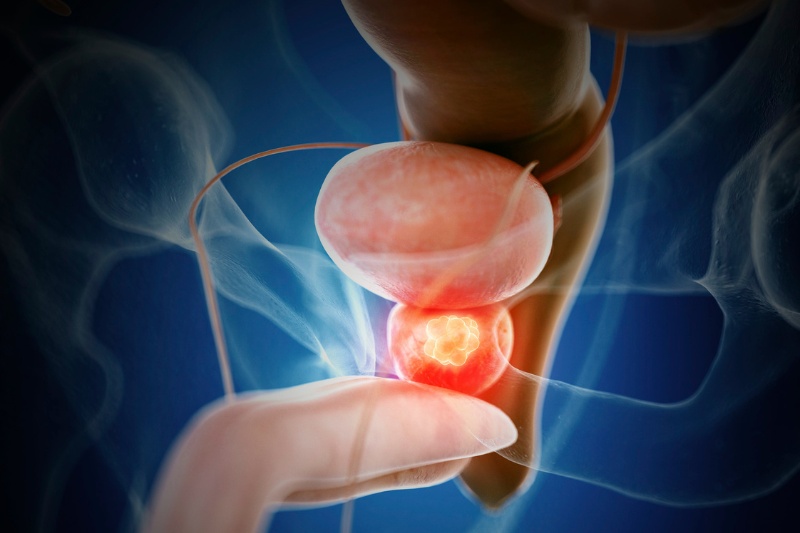

Ung thư tiền liệt tuyến

Ung thư tiền liệt tuyến là loại ung thư phát triển từ tế bào trong tuyến tiền liệt. Đây là loại ung thư phổ biến nhất ở nam giới và thường phát hiện ở những người trên 50 tuổi. Các triệu chứng của ung thư tiền liệt tuyến có thể bao gồm khó tiểu, tiểu nhiều lần trong ngày, tiểu buốt hoặc cảm giác đau khi tiểu, khó khăn trong việc giữ lại nước tiểu, đau lưng, xương chậu hoặc các triệu chứng khác liên quan đến đường tiết niệu.

Theo báo cáo vừa ghi nhận mới nhất cho biết tỷ lệ sống sót của nam giới mắc ung thư tiền liệt tuyến sau 5 năm là khoảng 99% nếu phát hiện sớm. Tuy nhiên, nếu ung thư tiền liệt tuyến đã lan sang các cơ quan và mô khác trong cơ thể, tỷ lệ sống sót sẽ thấp hơn rất nhiều.